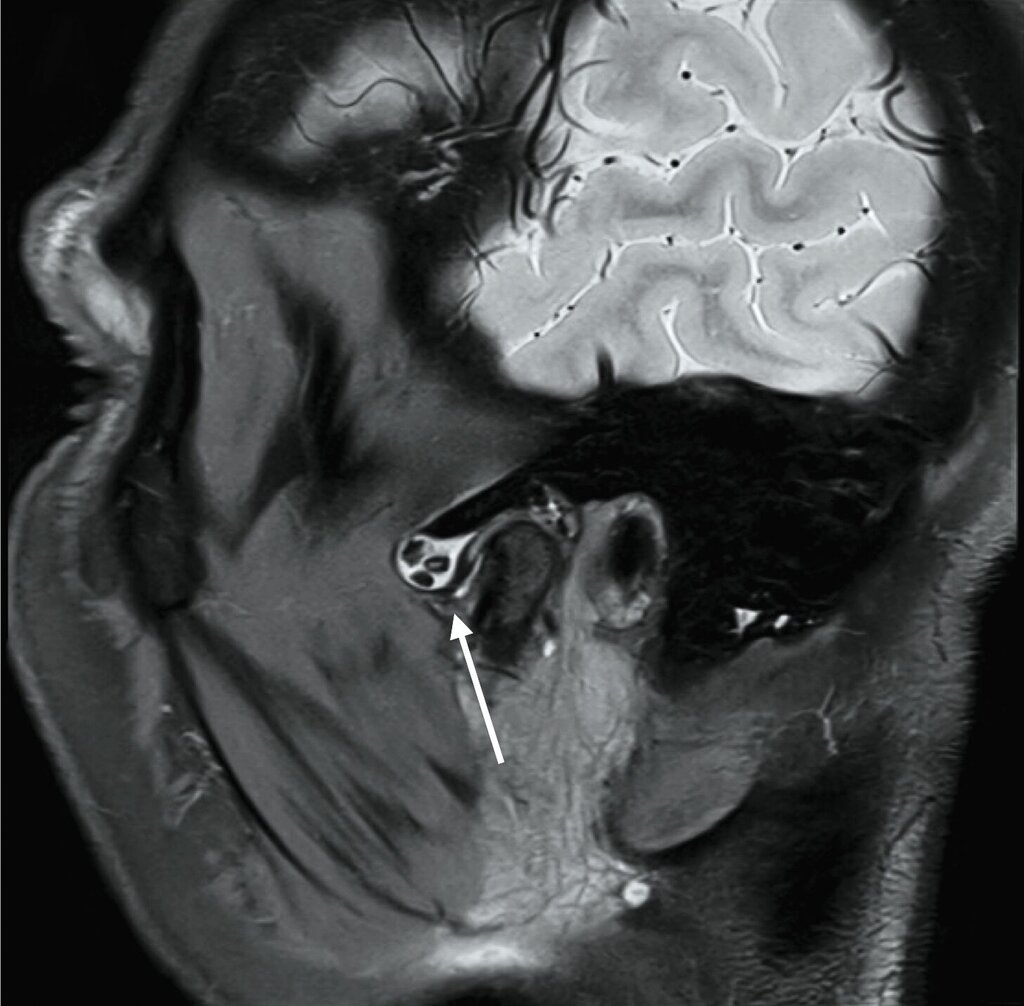

Bei nunmehr erhärteter radiologischer Verdachtsdiagnose auf das Vorliegen einer synovialen Chondromatose erfolgte, entsprechend dem Patientenwunsch, die offen-chirurgische Resektion der multiplen Gelenkkörper in Intubationsnarkose. Der Zugang wurde klassisch präaurikulär mit einer temporalen Extension zum Schutz des Ramus temporalis des Nervi facialis gewählt (Abbildung 3a). Unmittelbar nach Eröffnung der Kiefergelenkkapsel entleerten sich rasch mehrere kleine, knorpelige Raumforderungen (Abbildung 3b), die im Rahmen des Eingriffs vollständig entfernt wurden (Abbildung 3c). Der erweiterte, nun leere obere Gelenkspalt ist in Abbildung 3d dargestellt.